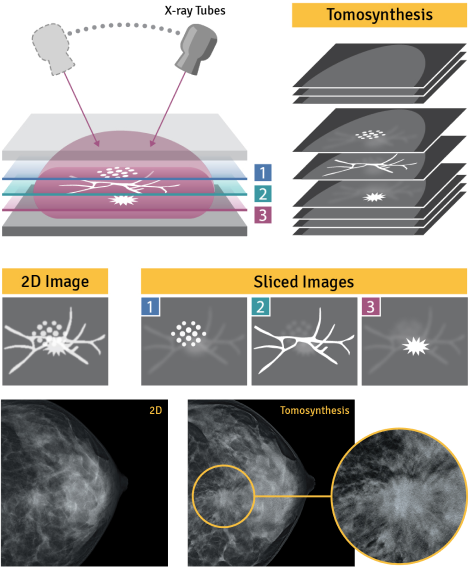

REiLi is our AI technology that uses deep learning and Fujifilm’s extensive image processing database to detect abnormalities automatically. This helps doctors accurately recognize the affected area and reduce the time taken by radiologists to interpret the scan.

A computerized tomography scan, more commonly called a CT scan, allows doctors to see internal organs in much greater detail than a regular X-ray. It takes a series of X-ray images at various angles around your body and processes it together to create multiple cross-sectional images (slices) of the scanned body part.